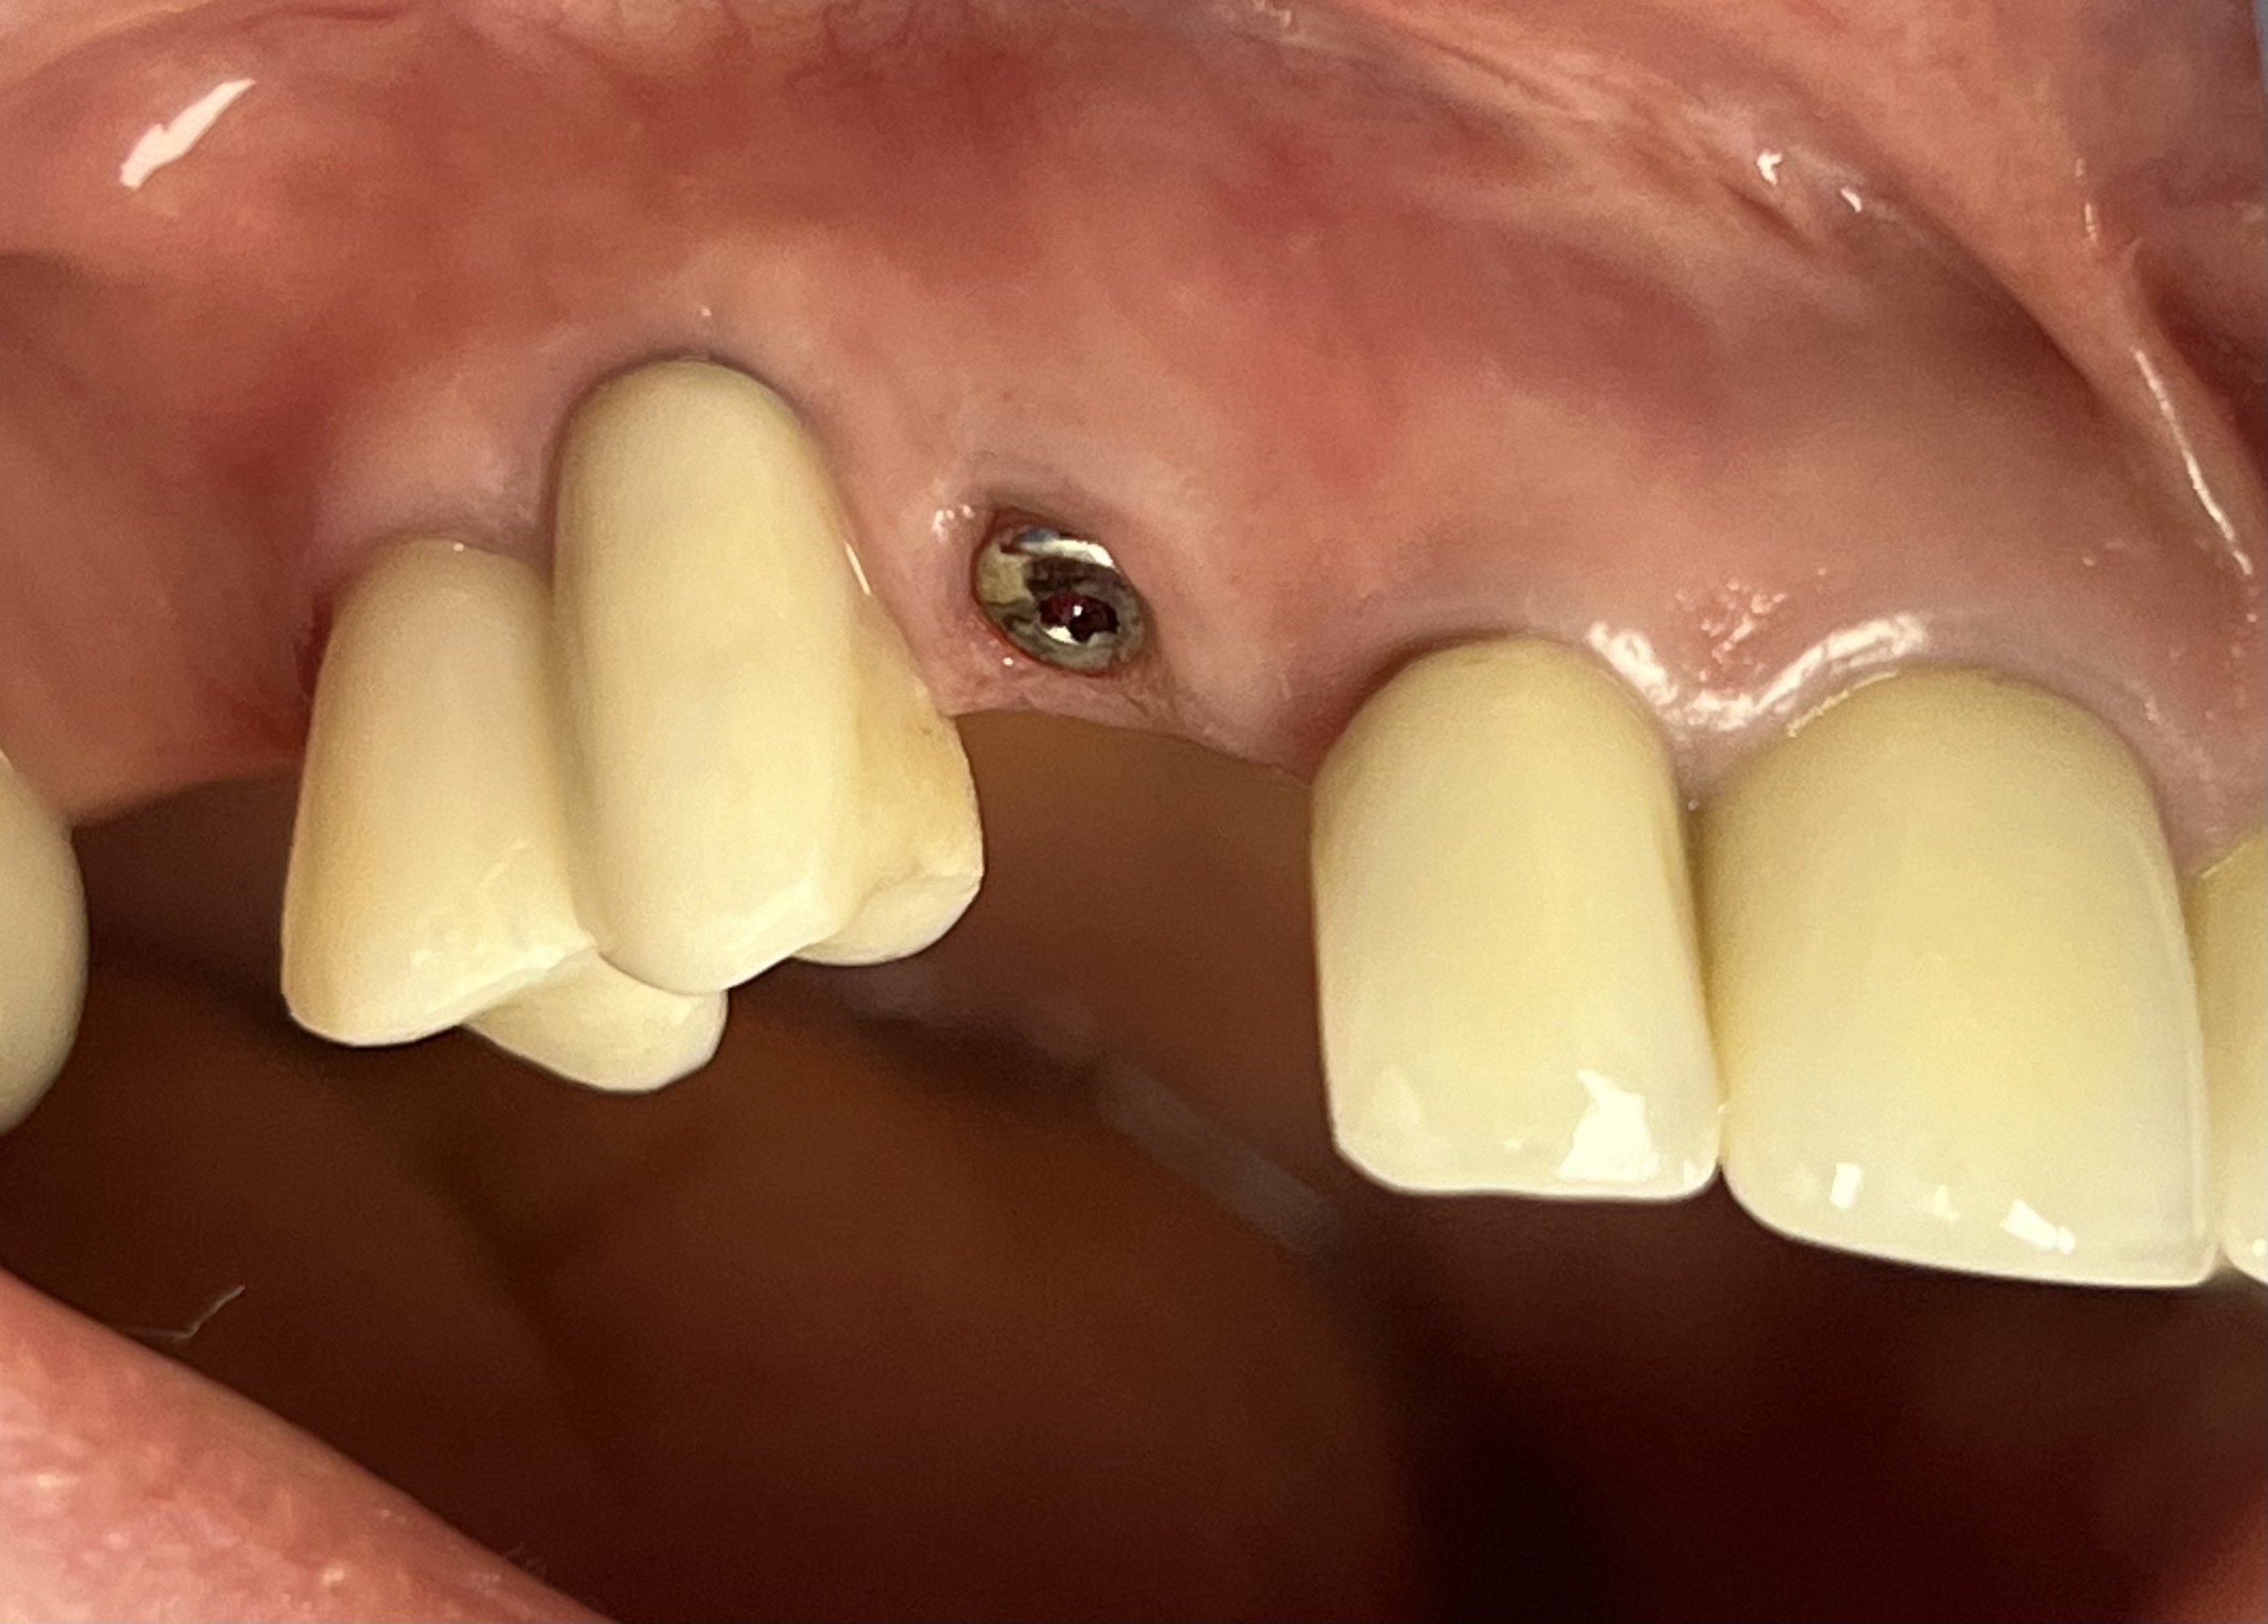

{Before} Implant Healing Cap #6

{After} Implant Crown #6